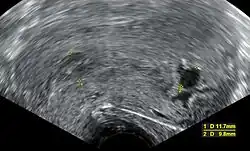

| An ultrasound showing a gestational sac containing a yolk sac but no embryo | |